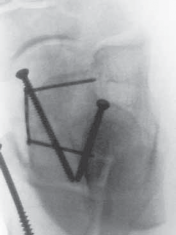

Finally, countersunk, interfragmentary small fragment (3.5 mm) screws or mini-plate and screw constructs are used to fix the talar neck fracture ( TECH FIG 3).

---

A B C TECH FIG 3 • A. Bone model depicting talar neck and dome fracture (AP view). B. Bone model depicting talar neck and dome fracture (lateral view). C. CT image of coronal talar body fracture.

TECHNIQUES D E F TECH FIG 3 •

(continued)

D. Postoperative fixation of talar body fracture requiring medial malleolar osteotomy. E. Postoperative lateral view of talar body fracture. F. Postoperative Canale view of talus. OPEN REDUCTION AND INTERNAL FIXATION OF THE POSTERIOR BODY OF THE TALUS